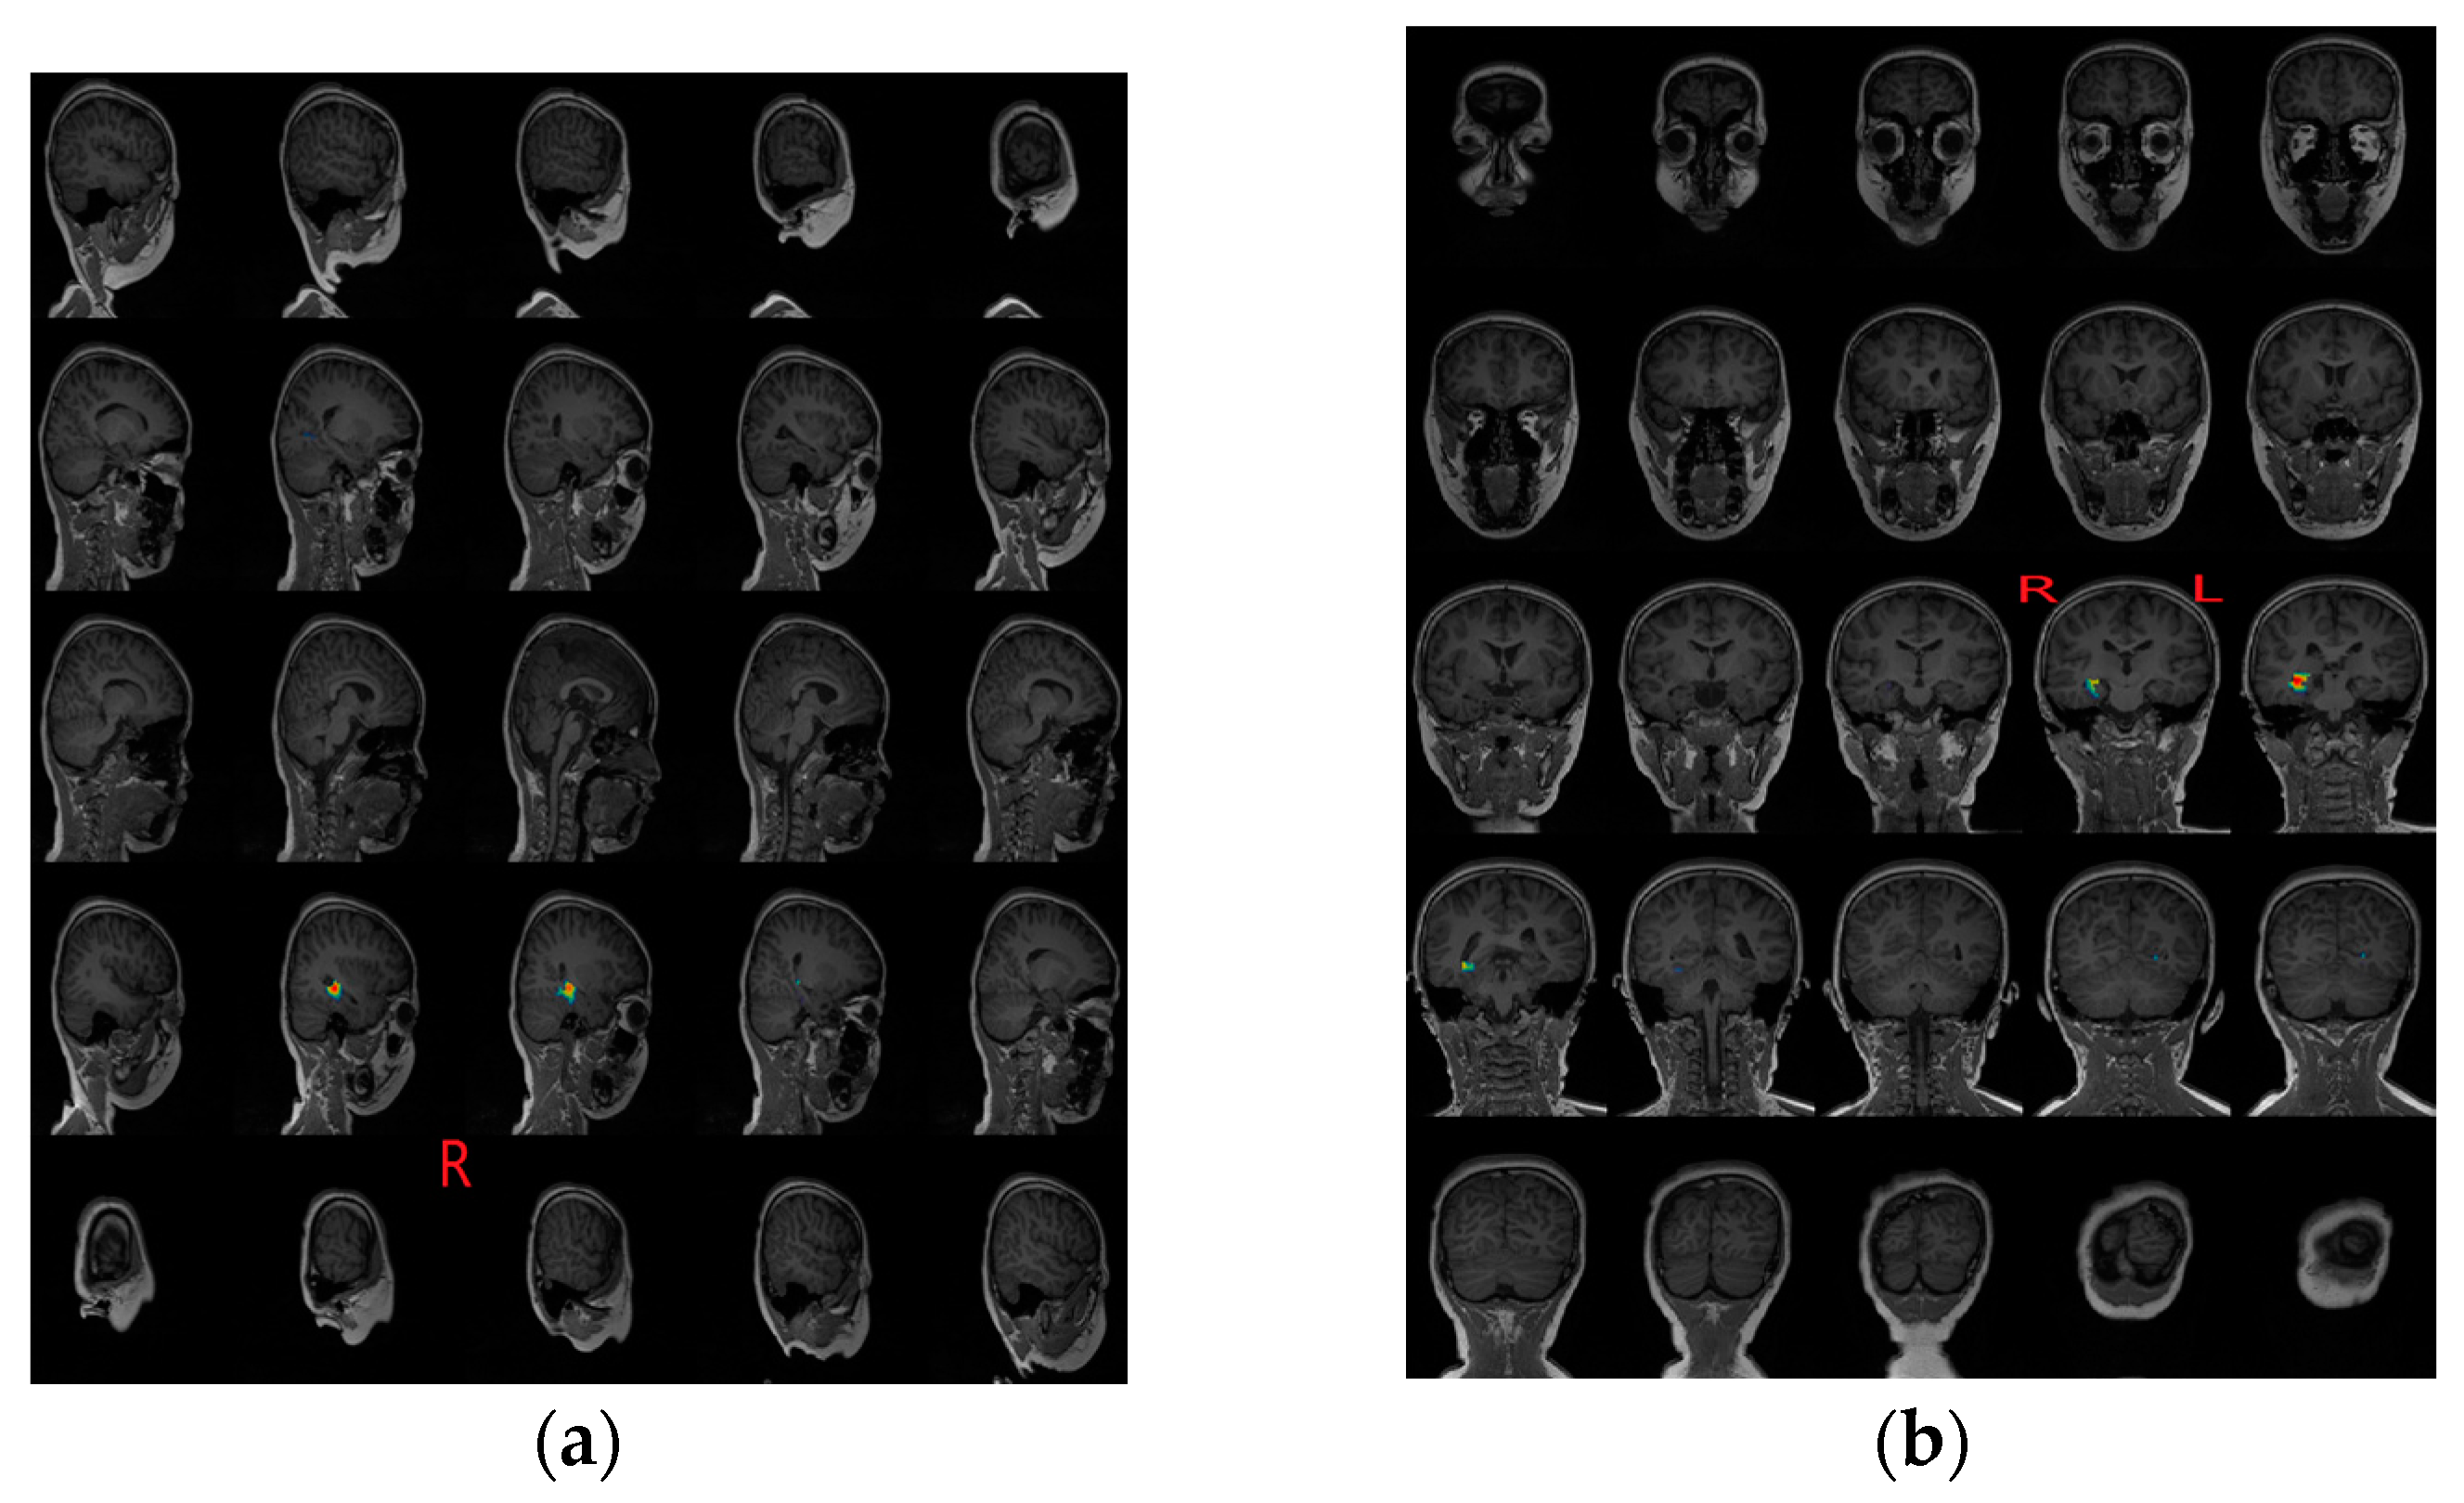

3.3. Epileptogenic Zone Localization Results